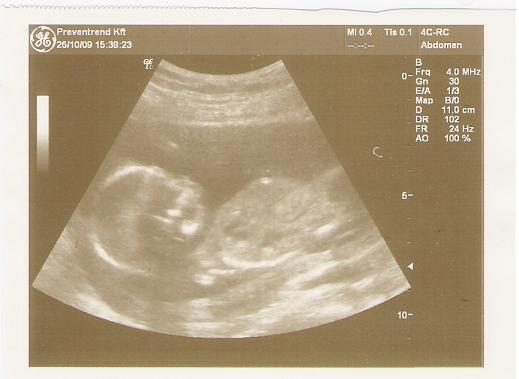

Pocaklakóm